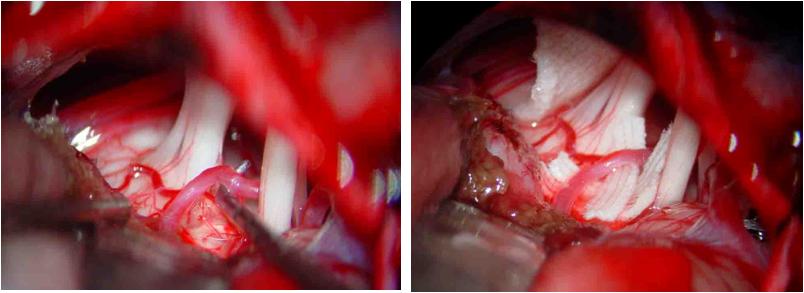

2. 三叉神经根的暴露在横窦下方剪开硬脑膜,向外下方延伸,然后折向内侧,硬脑膜瓣翻向中线,并在外上缘的硬脑膜上做附加小切口。悬吊硬脑膜,使横窦尽量向外上方牵开。用明胶海棉保护小脑,用宽1cm的脑压板伸入由小脑、小脑幕和岩骨嵴构成的三角内,并轻柔的翻起小脑的外上部。在手术显微镜下,锐性剪开岩静脉上的蛛网膜,用双极电凝镊电凝静脉后剪断。进一步翻开小脑,即可暴露面神经和位于其上方深处的三叉神经根和桥脑。

4. 微血管减压确认血管压迫三叉神经根后,用长柄微型剥离子把血管从神经上分开,在三叉神经前方垫入小块明胶海棉。取1cm×0.5㎝涤纶片,两端用剪刀修成锐角,在明胶海绵和三叉神经根之间插入,并向后环绕神经,用一枚银夹把涤纶片两端对合,使之如“领套”状围绕桥脑旁的三叉神经, 以便与周围的血管隔离。也可用涤纶片衬垫在血管和神经之间,生物胶固定之。